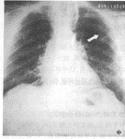

煤工塵肺2.X線檢查煤工塵肺胸片表現特徵有:網狀改變;結節狀改變;結節融合;塊狀陰影和多量絨毛狀改變。網狀改變被認為是煤工塵肺最早的表現,在肺野呈現瀰漫性細網狀陰影。而此時在臨床上無任何症狀。隨著結節的擴展,病變融合成不透明的進行性大塊纖維化,通常位於兩肺上野,也可跨肺葉融合至中、下肺野,有時僅發生在一側肺野,通常為大塊狀,均勻的、界限明顯的陰影。這些改變往往在單純性煤工塵肺彌散結節陰影的背景上發生。

伴有類風濕性關節炎的煤工塵肺患者,即Caplan綜合徵的胸部X線片往往呈現多個圓形、邊界清晰、分布較均勻的結節。在雙肺甚至分布至肺野周圍部分。圓形結節直徑可從0.5~5cm,但通常為1cm左右。有時病變出現與關節炎並無明顯相關性,或開始出現關節炎後病情迅速發展。在Caplan肺部病變可出現中心空洞,鈣化以及病變融合現象。在進行性大塊纖維化患者或有重度吸菸史者多合併有肺氣腫,嚴重肺氣腫往往致使肺部點狀和小結節顯示不清,易導致臨床醫生對病變